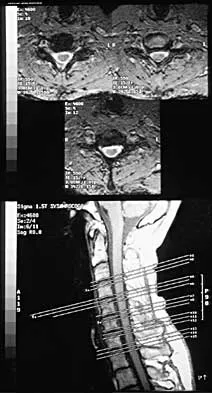

Figure 35 shows the radiograph of a 44-year-old woman with rheumatoid arthritis who reports neck pain. Below what threshold number is surgical stabilization warranted for the interval shown by the arrow?

Explanation

A 68-year-old woman with a history of rheumatoid arthritis has had neck pain and weakness in all four extremities that has become worse in the past 6 months. She has gone from a community to a household ambulator and uses a wheelchair outside of the home. Examination of the extremities reveals poor coordination, diffuse weakness, hyperactive reflexes, and bilateral sustained clonus. She has a broad-based and unsteady gait. The posterior atlanto-dens interval is 12 mm. Based on these findings and the radiograph and MRI scan shown in Figures 13a and 13b, the treatment of choice is surgical decompression and stabilization. However, the patient inquires about the prognosis with surgery compared to nonsurgical management. Assuming there are no complications from surgery, the patient should be informed that, with surgery, she will most likely

Explanation